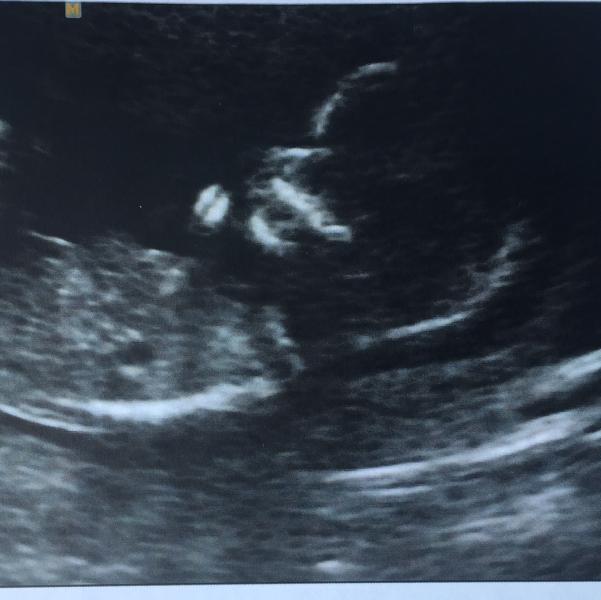

Ну вот и позади наш первый скрининг!🎉 Проходили дважды (при ЖК и в ЦИРе) Малыш был очень активным, открывал ротик, сжимал и разжимал кулачки, постоянно крутился, в общем продемонстрировал все что может на радость родителям)) записали диск для папы, теперь это любимый фильм👍

С анализами все хорошо, мы счастливы!!!

Знакомьтесь, это наш мальчик😀

Спасибо! Да, в обоих осмотрах сказали мальчик. Я ЖК не сильно доверяла, а вот в ЦИРе врач Тё УЗИ делал, а он говорят никогда не ошибается. Проверим)